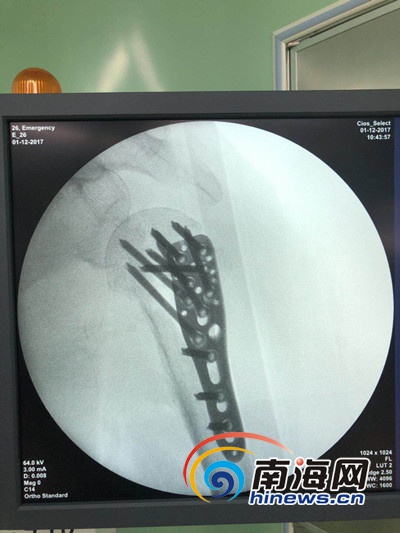

患者术后CT片。海口市骨科与糖尿病医院供图

海口市骨科与糖尿病医院副主任医师周祖彬是该手术的主刀医生。据其介绍,患者被送至医院后脸部有多处挫伤,手腕关节及肩部骨折。经检查,患者肩部为肱骨近端粉碎伴脱位骨折,该骨折是同部位最严重的骨折。

“手术难度较大,相对少见。作为我本人而言每年也仅做一两台这样的手术。患者摔伤严重,有高血压、糖尿病等慢性病。”周祖彬告诉记者,患者可以采取两种方案进行治疗,一种为换关节,而另一种用原来的关节,如果换关节,不仅费用高,而且病人的肩关节功能也将丧失一部分。经过会诊,患者用原来的关节最好,手术采用切开复位内固定术,解刨复位。

“两个手术一共用了两个多小时,手术比较顺利,出血不多。”周祖彬说,手术当中切口为12厘米,创伤面小,而且对周围组织的损伤小。